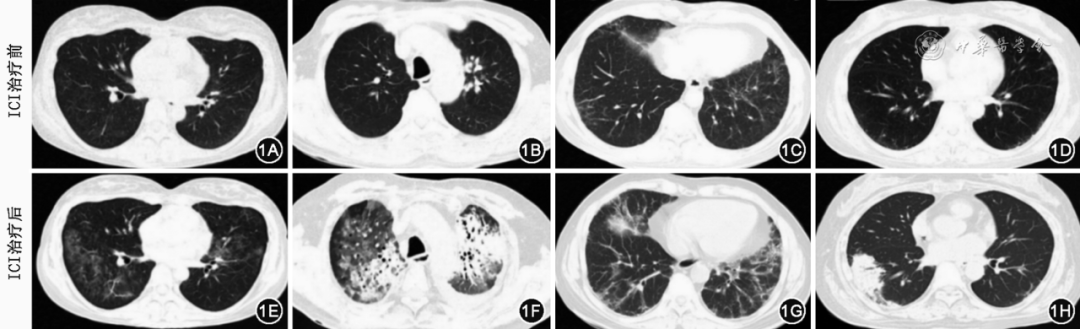

CIP是药物相关间质性肺炎,胸部影像学中的胸部CT是诊断CIP必要的关键的检查,也是评价CIP严重程度和评价预后的重要客观方法。与其他间质性肺疾病(ILD)类似,胸部高分辨率CT(HRCT)能更好地评价CIP的形态学特征。常规推荐胸部HRCT作为CIP诊断评价的首要检查。CIP患者的胸部CT影像学表现多样(图1),主要包括机化性肺炎样改变、非特异性间质性肺炎样改变、过敏性肺炎样改变、弥漫性肺泡损伤(急性间质性肺炎或急性呼吸窘迫综合征)样改变和普通型间质性肺炎样改变等。此外,肺炎的影像学类型可能与临床严重程度和分级相关,如弥漫性肺泡损伤(急性间质性肺炎或急性呼吸窘迫综合征)样改变提示较高级别的肺炎以及较差的临床预后,其次是机化性肺炎样改变,而非特异性间质性肺炎样改变和过敏性肺炎样改变与较低级别的肺炎相关。胸部CT还可表现为其他免疫相关肺损伤模式,包括胸膜病变(胸膜增厚、胸腔积液或多浆膜腔积液),肺结节病样肉芽肿性反应和胸内淋巴结肿大等。一般不推荐常规开展造影剂增强检查,但若疑诊并发肺栓塞时,建议尽早行CT肺动脉造影(CTPA)联合 CT静脉造影(CTV)检查。PET-CT在CIP的诊断和随访中的作用尚不清楚,因为PET-CT对于CIP、恶性肿瘤以及感染的鉴别诊断缺乏特异性,因此不常规推荐PET-CT作为CIP诊断评价的手段。

图1  免疫检查点抑制剂(ICI)相关间质性肺炎常见影像学表现

注:其中图1A、1E为非特异性间质性肺炎型,图1B、1F为弥漫性肺损伤型,图1C、1G为非特异性肺炎合并机化性肺炎,图1D、1H为机化性肺炎型